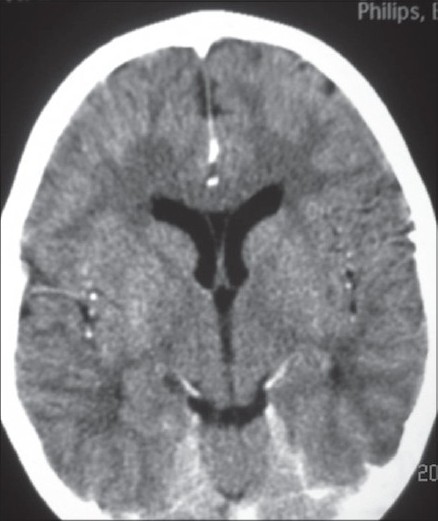

Routine hemogram, blood gas and serum electrolytes were normal. A CT and lumbar puncture were performed in view of focal seizures and no improvement of sensorium after 4 hours of admission. CT was performed before lumbar puncture and showed ill-defined hypodensities (CT value 16-23 HU) in the subcortical white matter in the posterior parietal lobes bilaterally suggestive of encephalitis [Figure 1]. Lumbar puncture showed 40 cells/mm 3 , proteins were 48 mg/dl and glucose was 71 mg/dl with no organisms seen on gram stain. A chest X-ray revealed a small focal consolidation in the right lower zone. Nasopharyngeal aspirate specimen tested for H1N1 by RT-PCR tested positive. CSF was negative for H1N1 (by RT-PCR). CSF PCR for Herpes simplex virus was negative. Additional viruses such as enterovirus, varicella zoster, cytomegalovirus and Epstein-Barr virus tests could not be done due to financial constraints. Broad spectrum IV antibiotic, oseltamivir and acyclovir treatment were initiated. EEG showed evidence of focal slowing and sharp activity from the left centroparietal region [Figure 2]. The sensorium improved after 48 h and there were no further seizures. The patient was given oseltamivir for five days. He was discharged after 10 days of hospitalization.

Figure 1 :CT brain showing ill-defi ned hypodensities in subcortical white matter in both parietal lobes.

Kimura et al divided influenza-related brain changes into five categories based on the MR imaging and CT findings: normal (category 1), diffuse involvement of the cerebral cortex (category 2), diffuse brain edema (category 3), symmetric involvement of the thalamus (category 4), and focal encephalitis (category 5). Our patient's CT findings are consistent with category 5 i.e. focal encephalitis. Lyon et al. reported CT and MR imaging findings in a 12-year-old girl infected with influenza A (H1N1) whose clinical course was complicated by acute necrotizing encephalopathy. The authors reported T2 hyperintensity and restricted diffusion in the thalami, cerebellar hemispheres and brain stem. Haktanir A. reported similar abnormalities and also bilateral perirolandic changes and diffuse meningeal enhancements.